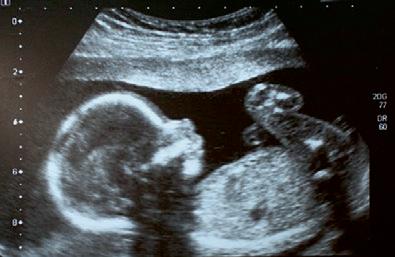

»Fostergave« er et af disse ord, som vi støder på i salmen om vintergækken.

Ordet »foster« kender vi som benævnelsen for det ufødte barn, men selve ordet fostergave har Simon Grotrian selv opfundet. Vi kan ikke spørge ham, hvad han mente med det, for han døde i 2019, men det står én frit for at smage på ordet og se, hvilken mening, det kan rumme.

Det er nærliggende at tænke, at han med fostergave forestiller sig, at Guds nåde også gælder for det

lille barn som en gave, det modtager allerede i fostertilstanden.

Dermed rammer han meget godt, hvad der menes med udtrykket Guds nåde. Ordet nåde kommer af det græske gratia, som betyder gratis. Nåden er altid gratis og er altid givet på forhånd. Guds nåde er et udtryk for hans kærlighed, som han giver betingelsesløst til alle mennesker. Derfor siger man, at nåden skænkes os ufortjent.

Det lille foster kan jo vitterligt ikke gøre andet end at tage imod, og derfor er fostergave et fint og beskrivende ord for det, som er givet os fra den allerførste begyndelse som et menneskevilkår.